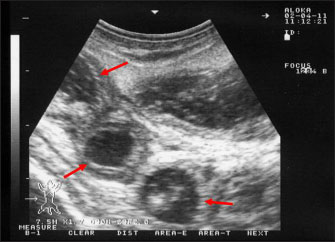

Ultrasonography has been proven effective for the early detection of several abdominal and thoracic disorders in small ruminants (Tharwat et al., 2012b; Tharwat and Al-Sobayil, 2017; Tharwat, 2021; Sadan et al., 2023; Tharwat and Al-Hawas, 2024a,b; Tharwat et al., 2024; Tharwat et al., 2025b). Recently, the technique has been found valuable for the diagnosis of various bacterial and parasitic infections in ruminants (Tharwat and Tsuka, 2024). An overall increase in intestinal mucosa thickness was detected in goats with PTB. It was classified as either mild, moderate, or severe (Fig. 2). Corrugation and folding of the intestinal mucosa may be also imaged in goats with PTB (Fig. 3). However, remarkable enlargement of the mesenteric lymph nodes are the most important findings in goats with PTB (Fig. 4). Other sonographic changes included increased hepatic brightness, intestinal edema consolidated lungs, and pleural, peritoneal, and pericardial effusions (Tharwat et al., 2012b).

Fig. 2. Ultrasonography of the thickened intestinal walls in a goat with paratuberculosis. Thickening of the intestinal mucosa is apparent cross sectionally (red arrows).